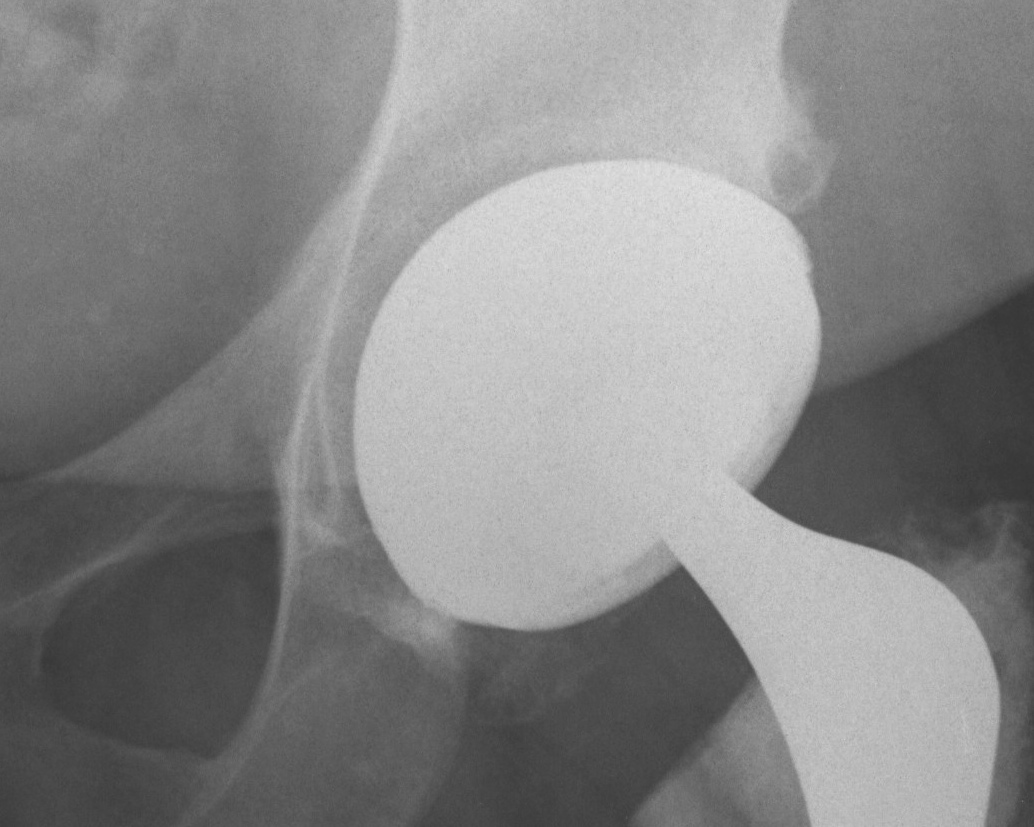

Poly wear

THR Poly WearTHR Eccentric Poly Wear